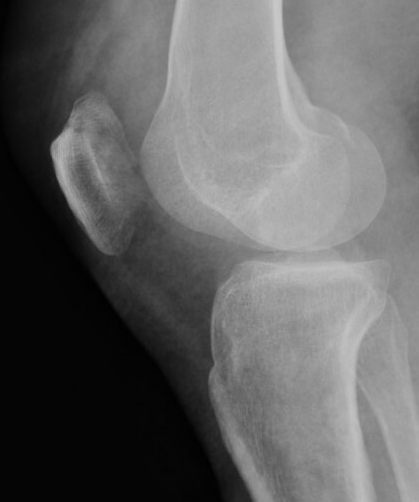

Xray

Look for osteochondral fractures

- lateral xray: notch

Loose body in notch with donor site from patella